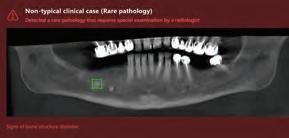

Clinical case no. 2

A 68-year old female patient interested in performing dental implants in the lower jaw came for an examination at the dental clinic and was subsequently referred to a CBCT scan. As part of the routine examination process in the clinic, the patient’s imaging files were uploaded to an artificial intelligence system (Diagnocat, Diagnocat Inc., USA) which

Figure 6: An OPG taken after placement of four implants in the patient’s lower jaw. Figure 7: Panoramic reformatting performed by artificial intelligence (Diagnocat, Diagnocat Inc., USA). A hypodense lesion is clearly seen in the furcation region of tooth 46. Figure 8: List of automatically generated diagnoses and sample slices provided by artificial intelligence. Figure 9: A built-in viewer enables easy creation of new slices and clear visualization of the furcational lesion. 10a. 3D segmentation was performed to appraise the bone defect treated by the lesion.

Figure 10b-d: Virtual extraction of tooth 46 (before the actual procedure) allows for a good appraisal of the damage caused by the furcational lesion and planning of the socket preservation / implant placement procedures that would follow the extraction.

indicated the presence of a lesion in the right posterior region of the lower jaw. (Fig. 4a-b) The mixed lesion, presenting a hyperdense core surrounded by hypodense shell, is most likely a fibro-osseous lesion, and in a joint consultation with an oral and maxillofacial surgeon, it was decided to leave it for follow-up at this stage. However, it was also decided that implant placement is possible mesial to the lesion.

Nevertheless, the patient still wants implants to be placed, and for this purpose, a three-dimensional segmentation was carried out to further examine the ridge anatomy and the possibility of designing a surgical guide that will allow the installation of implants mesial to the mixed lesion, which is also well visible in the 3D model. (Fig. 5a)

The 3D model also makes it possible to clearly and

sharply see the narrow shape of the patient’s residual ridge. (Fig. 5b-c) This information helped us plan the future treatment, as well as provide an exhaustive explanation to the patient and obtain informed consent for all stages of the procedure. (Fig. 6)